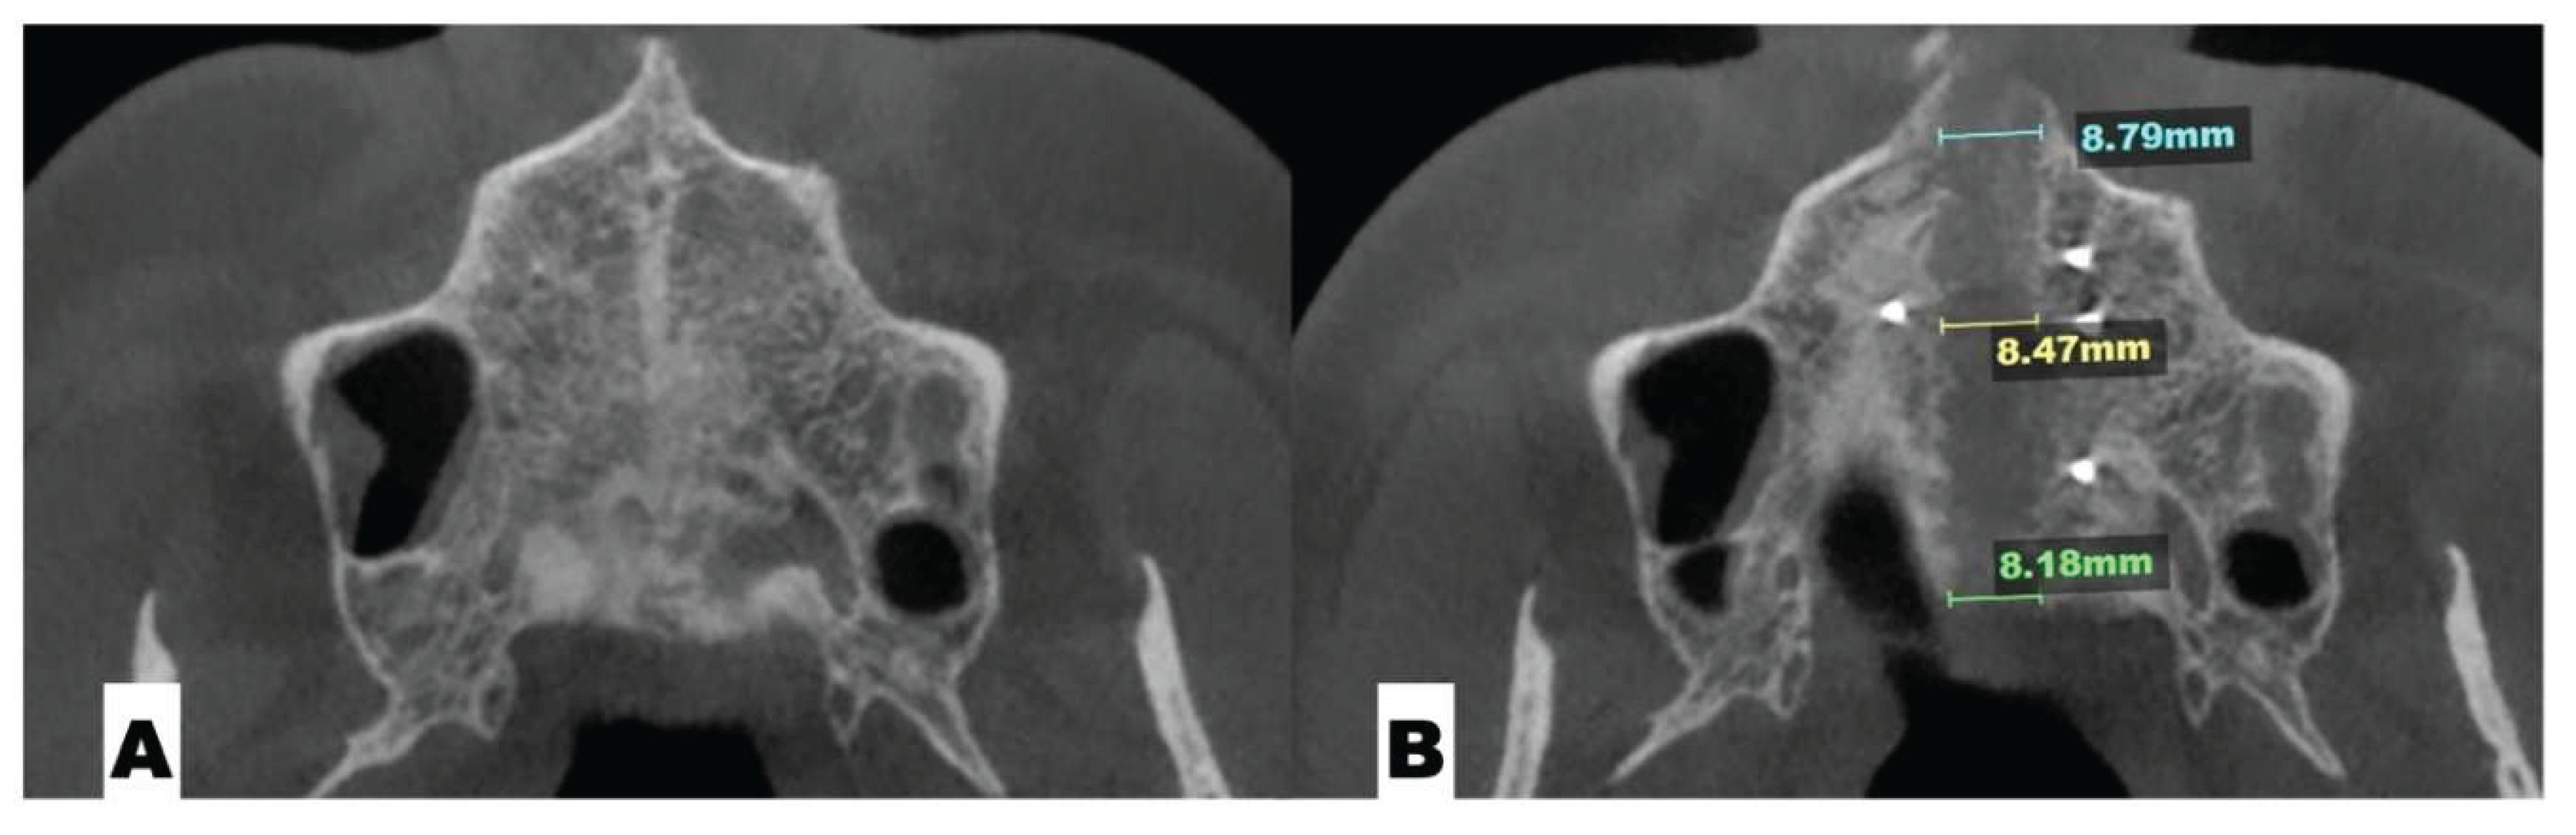

Background: While mini-screw-assisted rapid palatal expansion (MARPE) is effective for correcting maxillary transverse deficiency in adults, perimaxillary suture disarticulation—particularly at the pterygomaxillary junction—can be inconsistent. This study evaluates skeletal and dentoalveolar outcomes of a novel 3D-guided midpalatal piezocorticotomy-assisted MARPE protocol, focusing on expansion symmetry and pre-existing asymmetries. Methods: Three adult patients were retrospectively analyzed after treatment with 3D-guided midpalatal piezocorticotomy-assisted MARPE expansion and one with non-guided midpapalatal piezocorticotomy and MARPE expansion. Surgical guides were digitally designed using CBCT data to align with the nasal septum orientation in multiple planes. Perimaxillary suture disarticulation was measured pre- and post-expansion, and dentoalveolar changes were evaluated. Post-expansion asymmetries were addressed using directly printed aligners. Results: Complete midpalatal suture separation (mean 8.48 mm), involving both anterior and posterior nasal spine regions, was achieved in one patient. Bilateral pterygomaxillary disarticulation averaged 1.06–1.23 mm, resulting in forward–outward rotation of the nasomaxillary complex. Additional separation occurred at the frontonasal (2.03 mm) and vomeromaxillary (1–2 mm) sutures, with no significant changes in orbital or peri-orbital sutures. One patient presented with pre-existing dentoalveolar asymmetry, which intensified the perceived post-expansion imbalance but was successfully corrected with directly printed aligners. In the second case, 5.6 mm of suture separation resulted in a limited lateral nasal width increase (<1.5 mm), while maxillary base expansion exceeded 6 mm. A significant canine plane cant (1.2 mm) and divergent axial inclinations of the maxillary central incisors relative to the palatal plane were also observed. In the second case, a non-impactful palatal bone fracture with asymmetric displacement of the left palatine fragment was documented. After 16 months of aligner therapy, all cases exhibited favorable remodeling of the palatal structures, midpalatal suture, and alveolar processes, accompanied by improved dental alignment, occlusal plane symmetry, and mandibular dentoalveolar adaptation. The dento-alveolar expansion achieved in the third case over the course of 16 months of treatment was approximated at 4 mm. The fourth case showed consistent improvement with direct printed aligners after MARPE midpalatal diasrticulation of 11 mm after experiencing minor bone fracture. Conclusions: Human skulls exhibit considerable variability between the left and right sides, which can influence spatial balance. Pre-existing cranial asymmetries appear to be the primary contributors to asymmetry following MARPE treatment. Careful evaluation of dentoalveolar discrepancies and axial tooth inclinations is essential for preventing and managing potential asymmetric dental arch outcomes during the post-expansion phase. Although peri-maxillary bone fractures are relatively uncommon, their occurrence is influenced by multiple factors. Adjunctive techniques, such as 3D-guided midpalatal piezocorticotomy, show promise in significantly lowering the risk of intra-expansion peri-maxillary fractures.

| Suture nomenclature | Amount of disarticulation |

|---|---|

| Midpalatal | 8.48 mm |

| Palatinomaxillary (transverse) | none |

| Nasomaxillary | 1-2 mm |

| Zygomaticomaxillary | none |

| Lacrimomaxillary | none |

| Ethmoidomaxillary | none |

| Sphenomaxillary | none |

| Vomeromaxillary | 1-2 mm |

| Frontomaxillary | 2.5 mm |

| Pterygomaxillary | 1.06-1.23 mm |

| Frontonasal | 2.03 mm |

| Frontozygomatic | None |